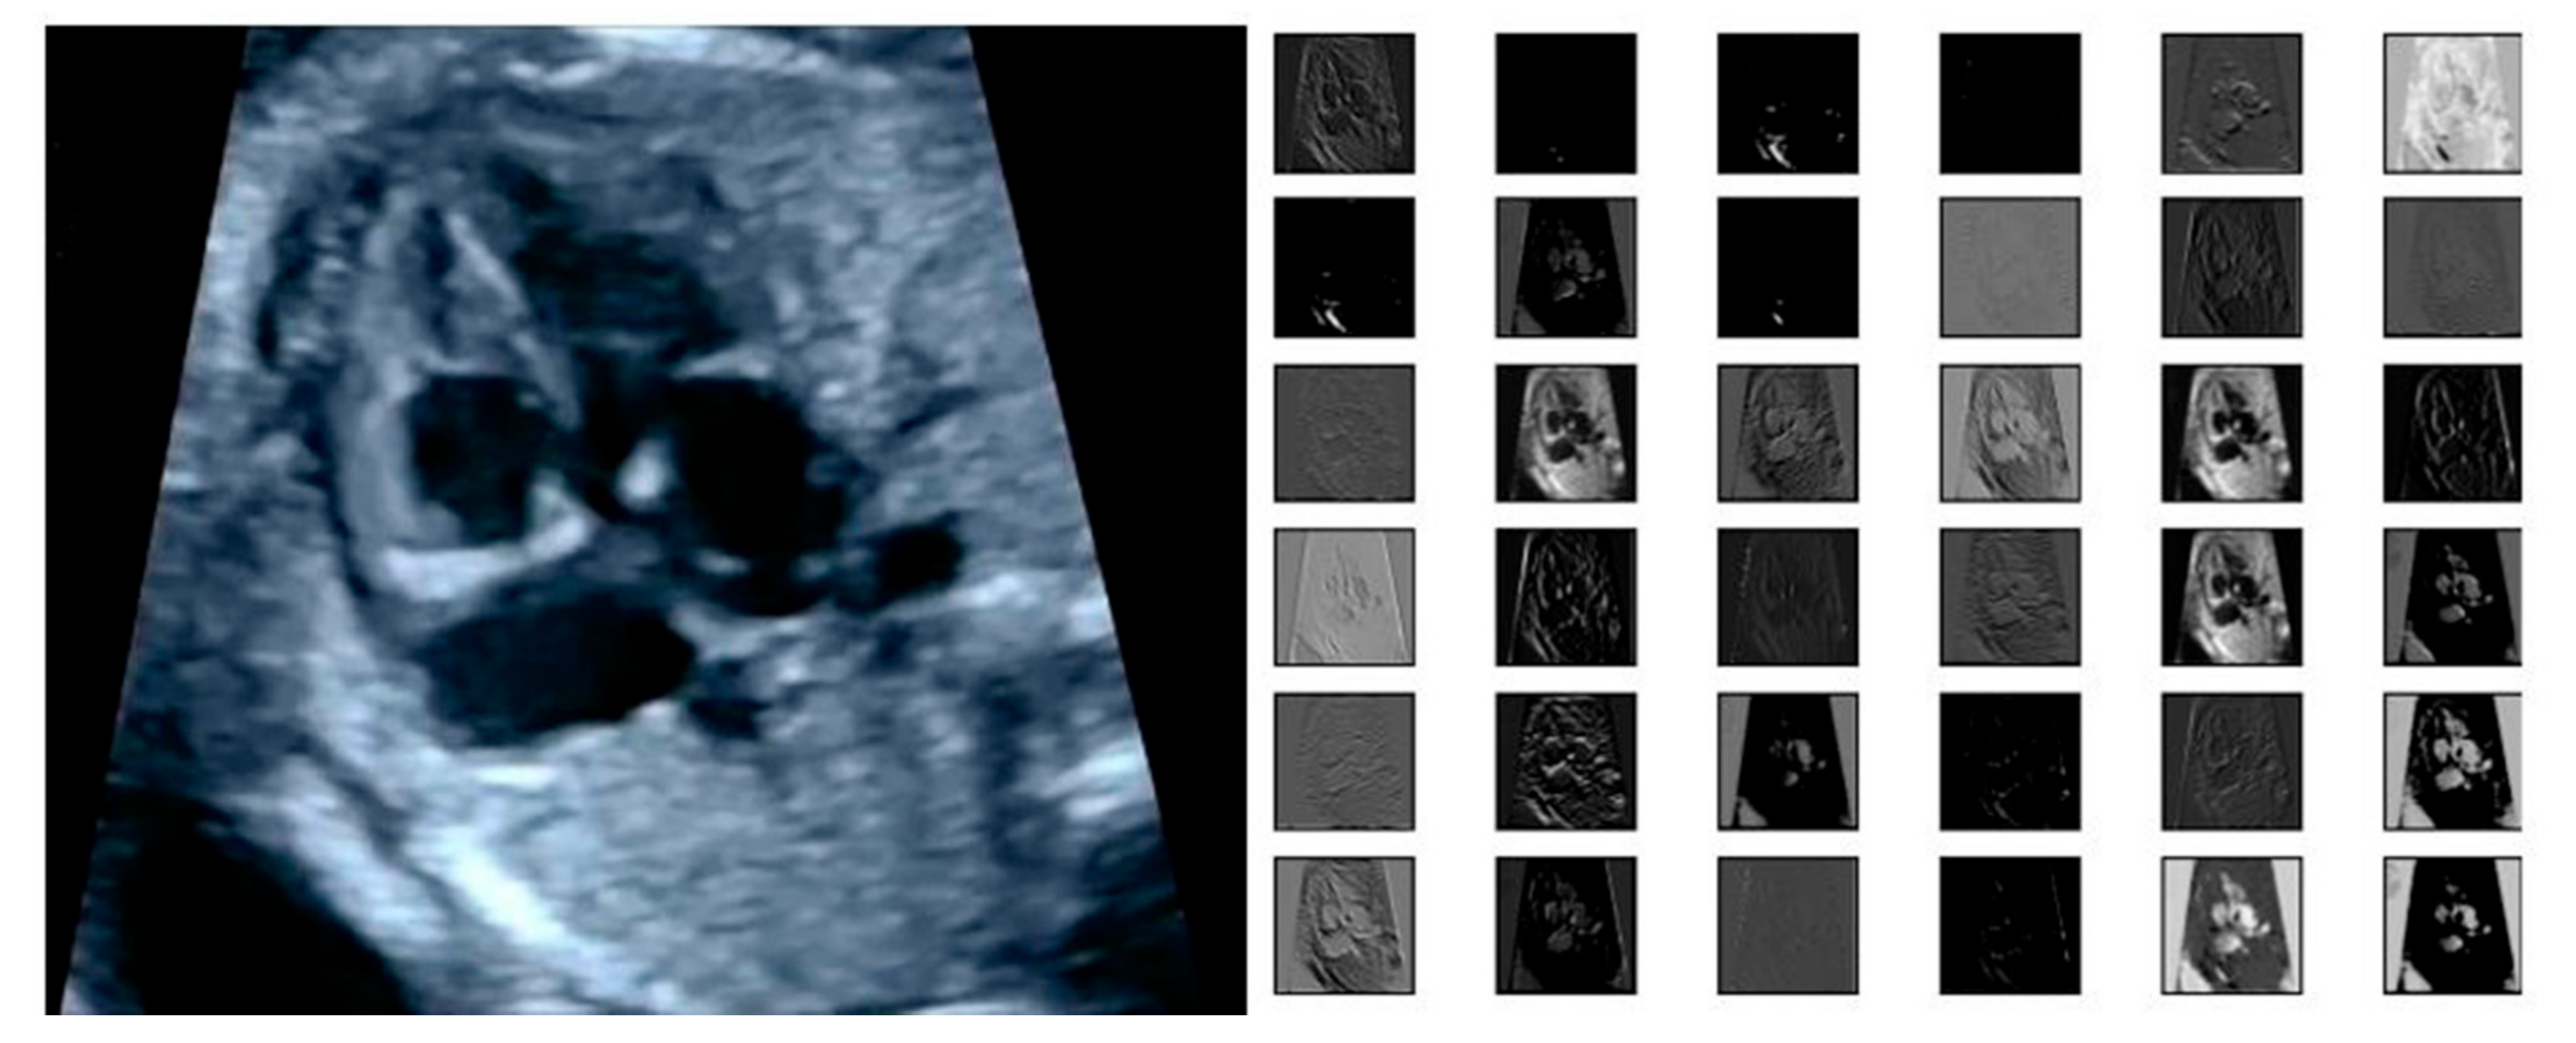

2.4.1. Region Proposal Networks

The input of the region proposal networks (RPNs) is 2D ultrasound images; all the fetal hearts have the same size of resolution around 400 × 300 pixels. The ResNet50 architecture was applied as the backbone in the RPNs for the feature extraction mechanism. It can represent more complex functions and learn features from different network levels, from edges (shallower layers) to very complex features (deeper layers). The RPNs use to generate RoIs, which will be used to predict classes and generate masks. Each RPNs had five convolutional layers, which were used to process high-level feature inputs to low-level outputs. The ResNet 50 structure as seen in Table 2, and the example feature map from ResNet 50 as seen in Figure 7.

Figure 7.

The example of feature map extracted from ResNet50 architecture in the RPNs back bone.